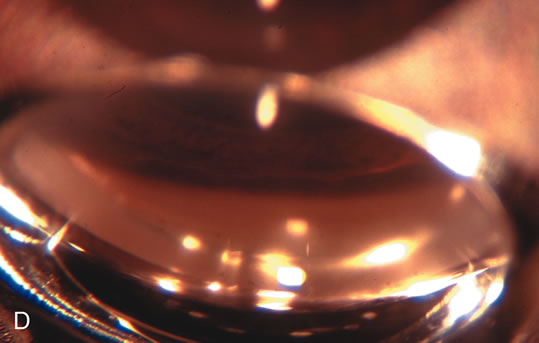

Fig. 3. Partial bleb failure following clear corneal phacoemulsification with foldable IOL. A. Preoperative bleb appearance prior to temporal lens extraction. Preoperative IOP was 12 mm Hg on no antiglaucoma medications. Time from 5-FU trabeculectomy surgery to lens extraction was one year. B. Bleb appearance 2 months after clear corneal cataract surgery with topical anesthesia. Following lens extraction, increased vascularity was noted along with decreased size of the filtering bleb. IOP increased to 20 mm Hg as early as 2 weeks after surgery, necessitating topical antiglaucoma therapy. C. High magnification view of bleb before lens extraction demonstrates diffuse pale bleb. D. High magnification view of bleb 2 months after surgery. There are vessels surrounding the nasal side of the bleb and the overall bleb size is smaller.

Fig. 1. The anatomic advantage of small incision cataract surgery for the glaucoma patient. A. Long-term bleb function with a large cataract incision is difficult to achieve with either ECCE-trabeculectomy or trabeculectomy followed later by ECCE. This bleb failed to form sufficiently when combined with large incision ECCE. The inflammation, bleeding, and long-term wound healing with stimulation of fibroblasts associated with this technique are more likely to cause bleb failure. In addition, the increased iris manipulation necessary to deliver the nucleus and subsequent iris repair adds to the long-term breakdown of the blood aqueous barrier. B and C. Two-site phacotrabeculectomy has the advantage of small incision cataract surgery combined with separate site trabeculectomy. The incision size is one third the size of the standard ECCE. The inflammation is less severe, and cataract wound healing is confined to the temporal area. Visual rehabilitation with phacoemulsification and foldable IOL is much faster. Phacoemulsification allows successful lens extraction even in the unfriendly environment of a smaller pupil compared with ECCE. The trabeculectomy is performed in an entirely different site, well away from the wound healing associated with temporal phacoemulsification. The likelihood of this filter functioning long-term is greater than with ECCE-trabeculectomy. D. The surgeon also has the option of single-site phacotrabeculectomy with foldable IOL. Both the lens extraction and trabeculectomy are performed through one small 3.5-mm limbal incision.